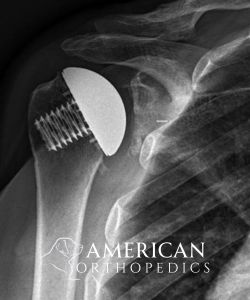

Reverse Total Shoulder for Rotator Cuff Arthropathy

Patient of Dr. Ratner.

After